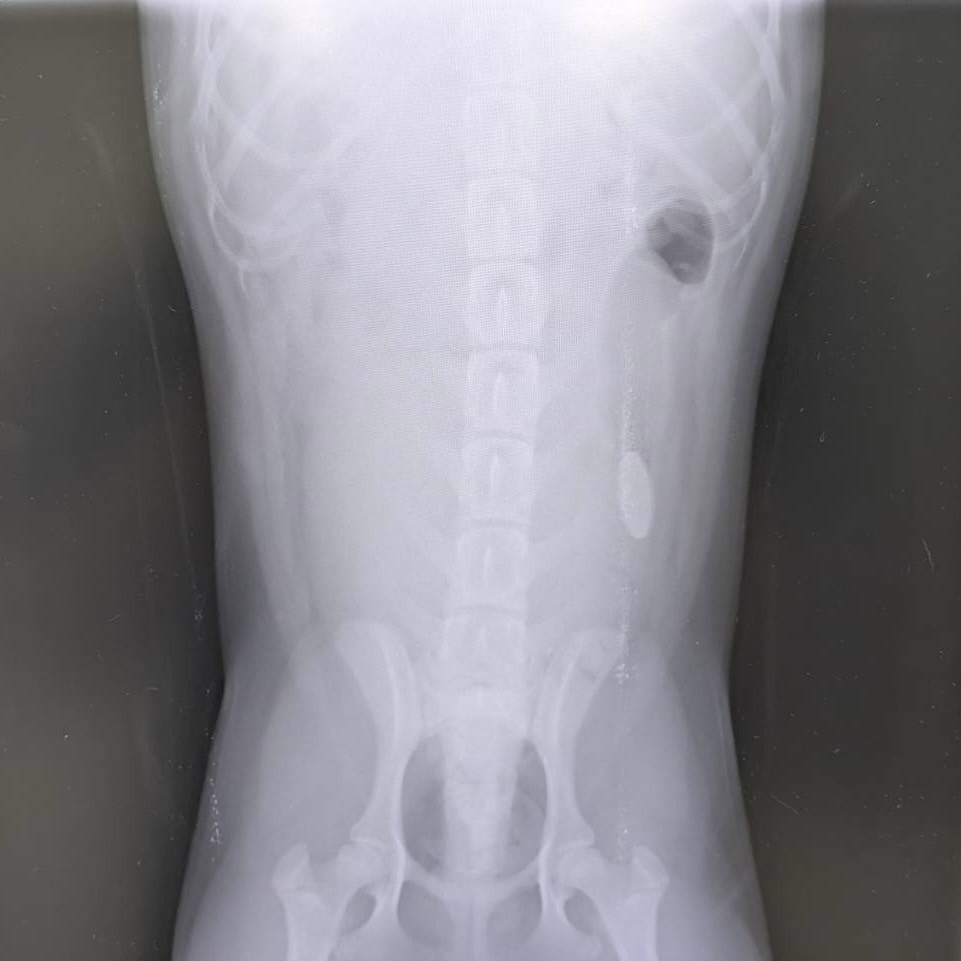

もしも誤食してしまったら

愛犬・愛猫が何かを食べてしまった…!